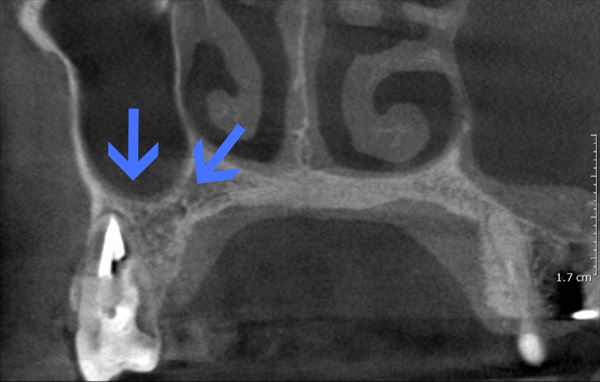

After

6ヶ月後のCT

洞底膜はきれいに再生され病巣は消失しております。